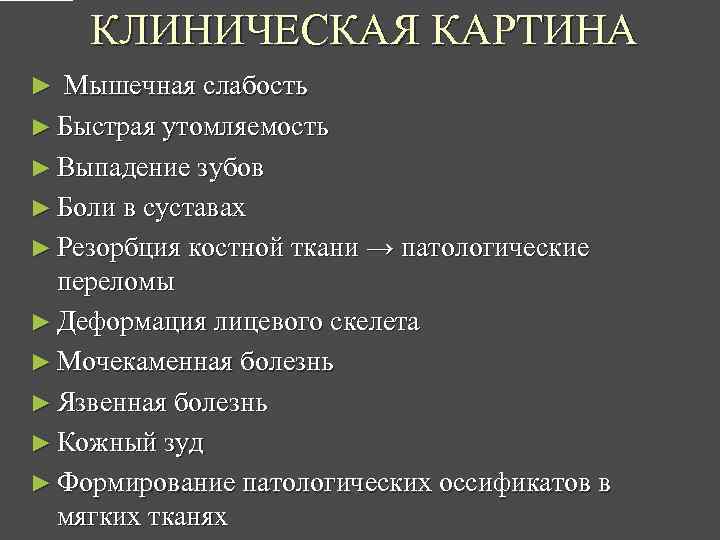

КЛИНИЧЕСКАЯ КАРТИНА ► Мышечная слабость ► Быстрая утомляемость ► Выпадение зубов ► Боли в суставах ► Резорбция костной ткани → патологические переломы ► Деформация лицевого скелета ► Мочекаменная болезнь ► Язвенная болезнь ► Кожный зуд ► Формирование патологических оссификатов в мягких тканях